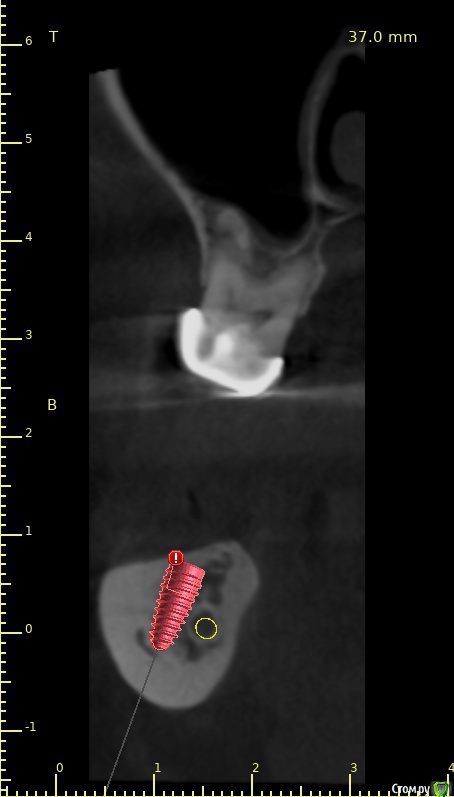

3й квадрант. Я могу обойти нерв. И даже выйти в более-менее приемлемую ортопедическую позицию.

Но очень смущает высота коронки и соотношение этой высоты к параметрам имплантата...

Премоляр под удаление и тоже имплантация. Ортопедические платформы будут находится на разном уровне...